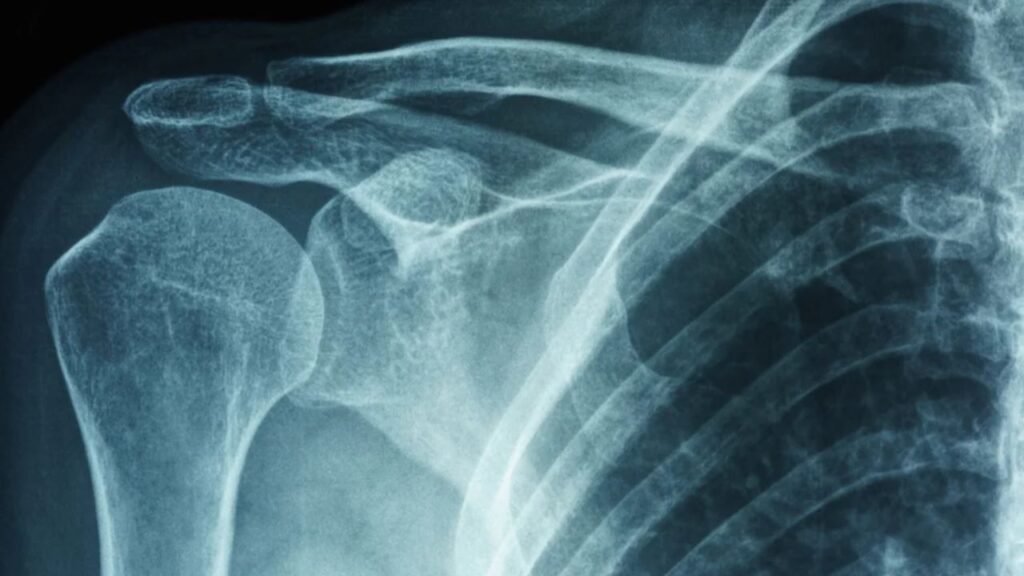

Para entender por que o ombro “congela”, precisamos olhar para a anatomia profunda da articulação. O ombro é envolvido por uma cápsula articular, um tecido elástico e flexível que contém o líquido sinovial e mantém os ossos no lugar. Na capsulite adesiva, essa cápsula sofre uma inflamação intensa, torna-se espessa, rígida e desenvolve aderências (cicatrizes internas). O resultado é que o espaço para o movimento do úmero diminui drasticamente, impedindo a rotação e a elevação do braço.

O diagnóstico é realizado pelo ortopedista através do exame clínico. Um sinal chave que diferencia o ombro congelado de outras lesões (como a do manguito rotador) é que o paciente não consegue mover o braço (movimento ativo) e o médico também não consegue mover o braço do paciente mesmo forçando levemente (movimento passivo), pois a cápsula está fisicamente retraída. Exames de imagem como a ressonância magnética ajudam a confirmar o espessamento da cápsula e descartar outras lesões.